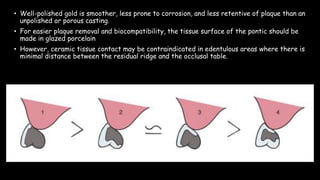

The document discusses pontic design for fixed dental prostheses. It covers pretreatment assessment of residual ridge contours, classifications of ridge deformities, surgical modification techniques, and ideal requirements for pontics. Pontic designs are classified based on their shape and materials. Factors in pontic selection include esthetics and oral hygiene. Common designs for anterior and posterior regions are described, including sanitary, ovate, and saddle pontics. Biological considerations for pontic design involve maintaining the residual ridge, abutment teeth, and supporting tissues.